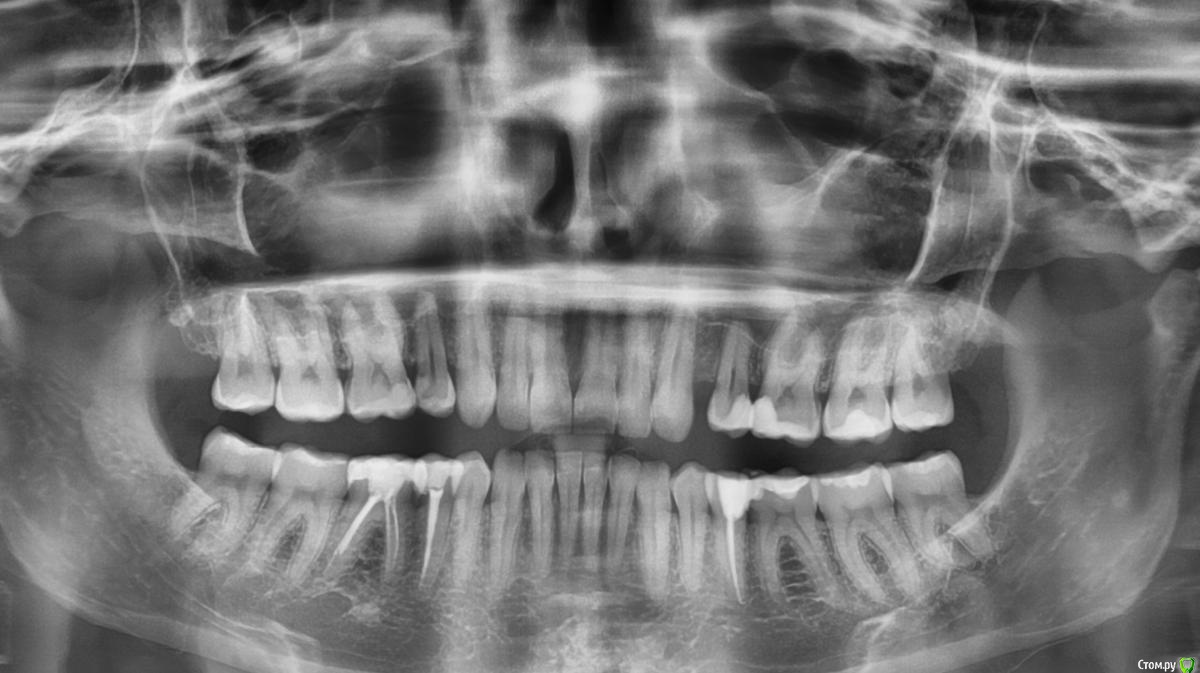

KatKy Опубликовано 25 октября, 2015 Автор Поделиться Опубликовано 25 октября, 2015 (изменено) Нет после пломбировки контрольный рентген не делали, стоматолог сказал не нужноА на что вообще похоже? Что может болеть, я не понимаю есть там воспаление или нет Есть вот такой рентген, на фотоаппарат сама сфоталаА по ОТПГ совсем ничего не видно? Изменено 25 октября, 2015 пользователем KatKy Ссылка на комментарий